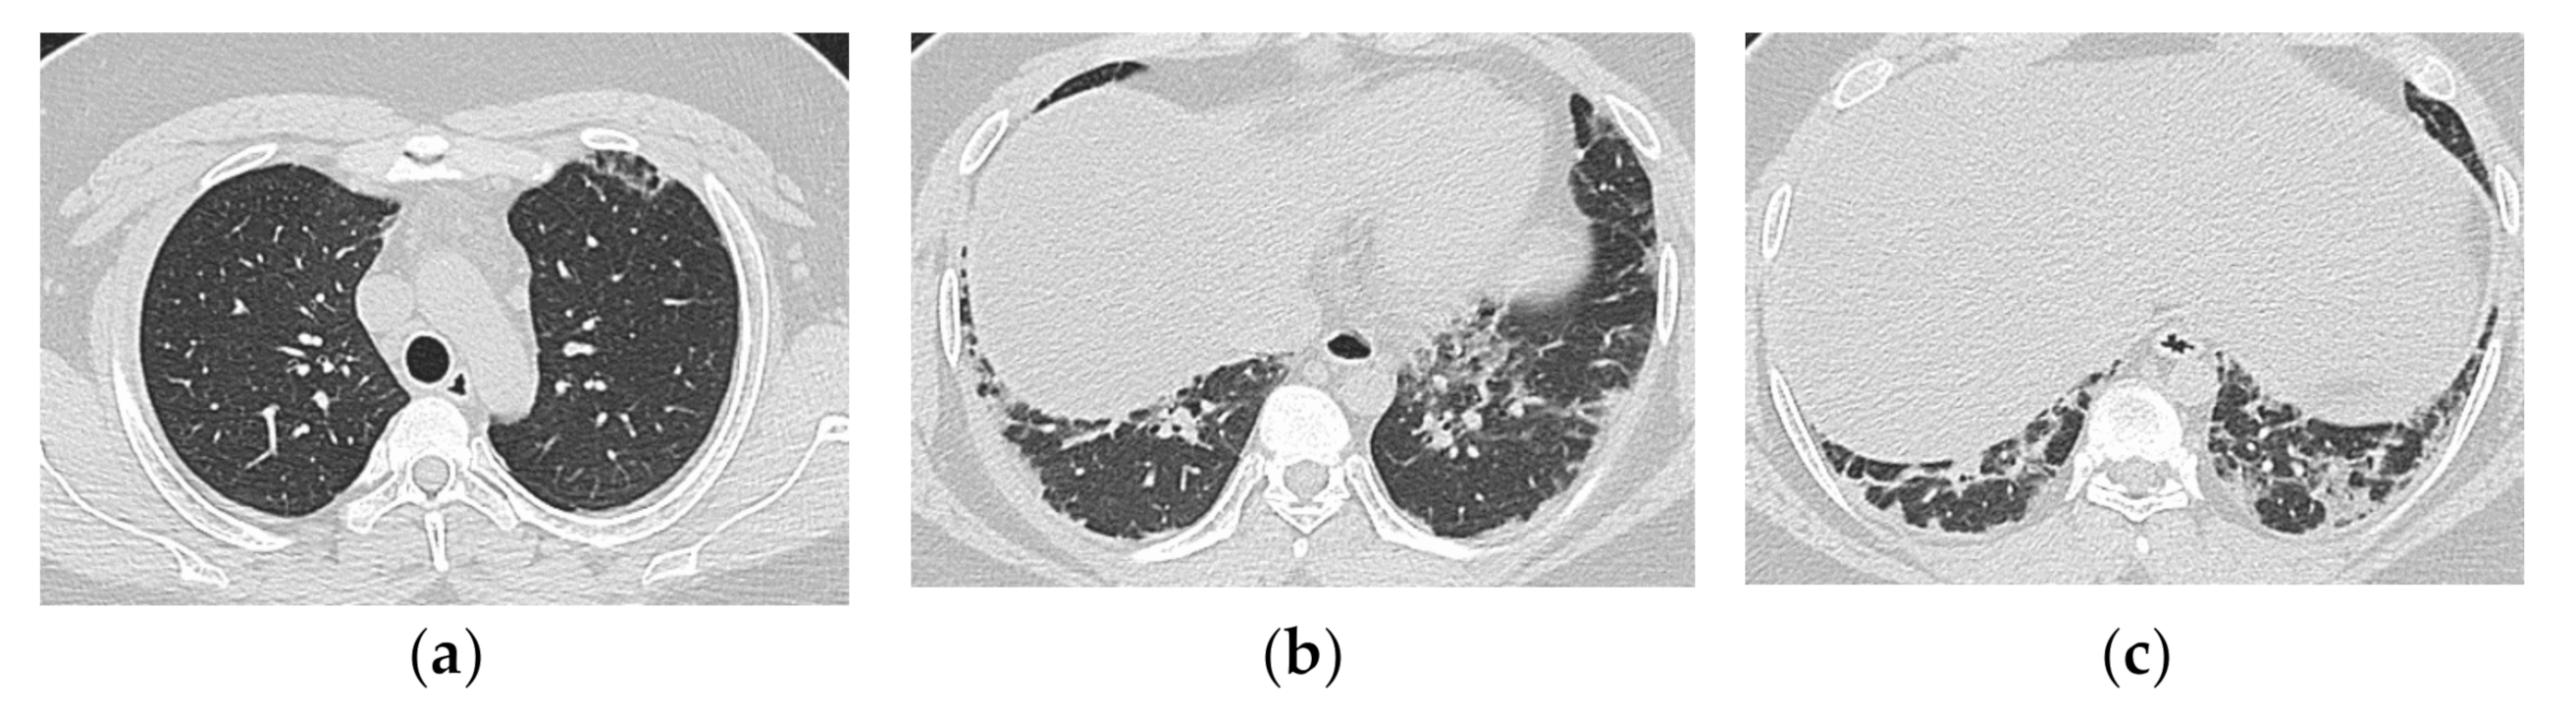

3.1. Anti-Aminoacyl tRNA Synthetase Antibody (Anti-ARS Ab)

HRCT Findings of Patients with Anti-ARS Ab

3.2. Anti-MDA5 Antibody (Anti-MDA5 Ab)

HRCT Findings of Patients with Anti-MDA5 Ab

| Anti-ARS Antibody Positive | Anti-MDA5 Antibody Positive |

|---|---|

| Chronic to subacute onset >> Acute/rapidly progressive | Acute or subacute onset, often rapidly progressive |

| Distribution along the bronchovascular bundles in the bilateral lower lung fields > diffuse | Diffuse, predominantly in the lower lung fields, or both |

| Reduced volume of the lower lobes | Peribronchovascular lesion of the periphery of lower lobes, with parallel spread to the pleura |

| Reticular shadows or consolidation > GGO | Patchy distribution |

| Good response to treatment but relapses | GGO and consolidation |